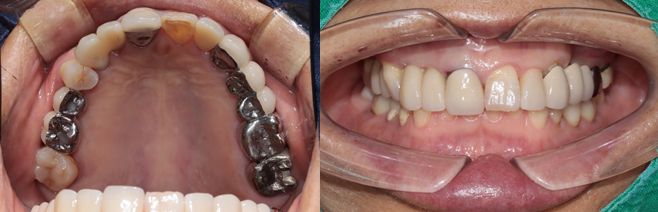

전치부는 지르코니아, 구치부는 보험임플란트 pfm 으로 제작 (70세 여자)

c.c: 앞니가 부러졌고, 오른쪽 어금니가 아파요.